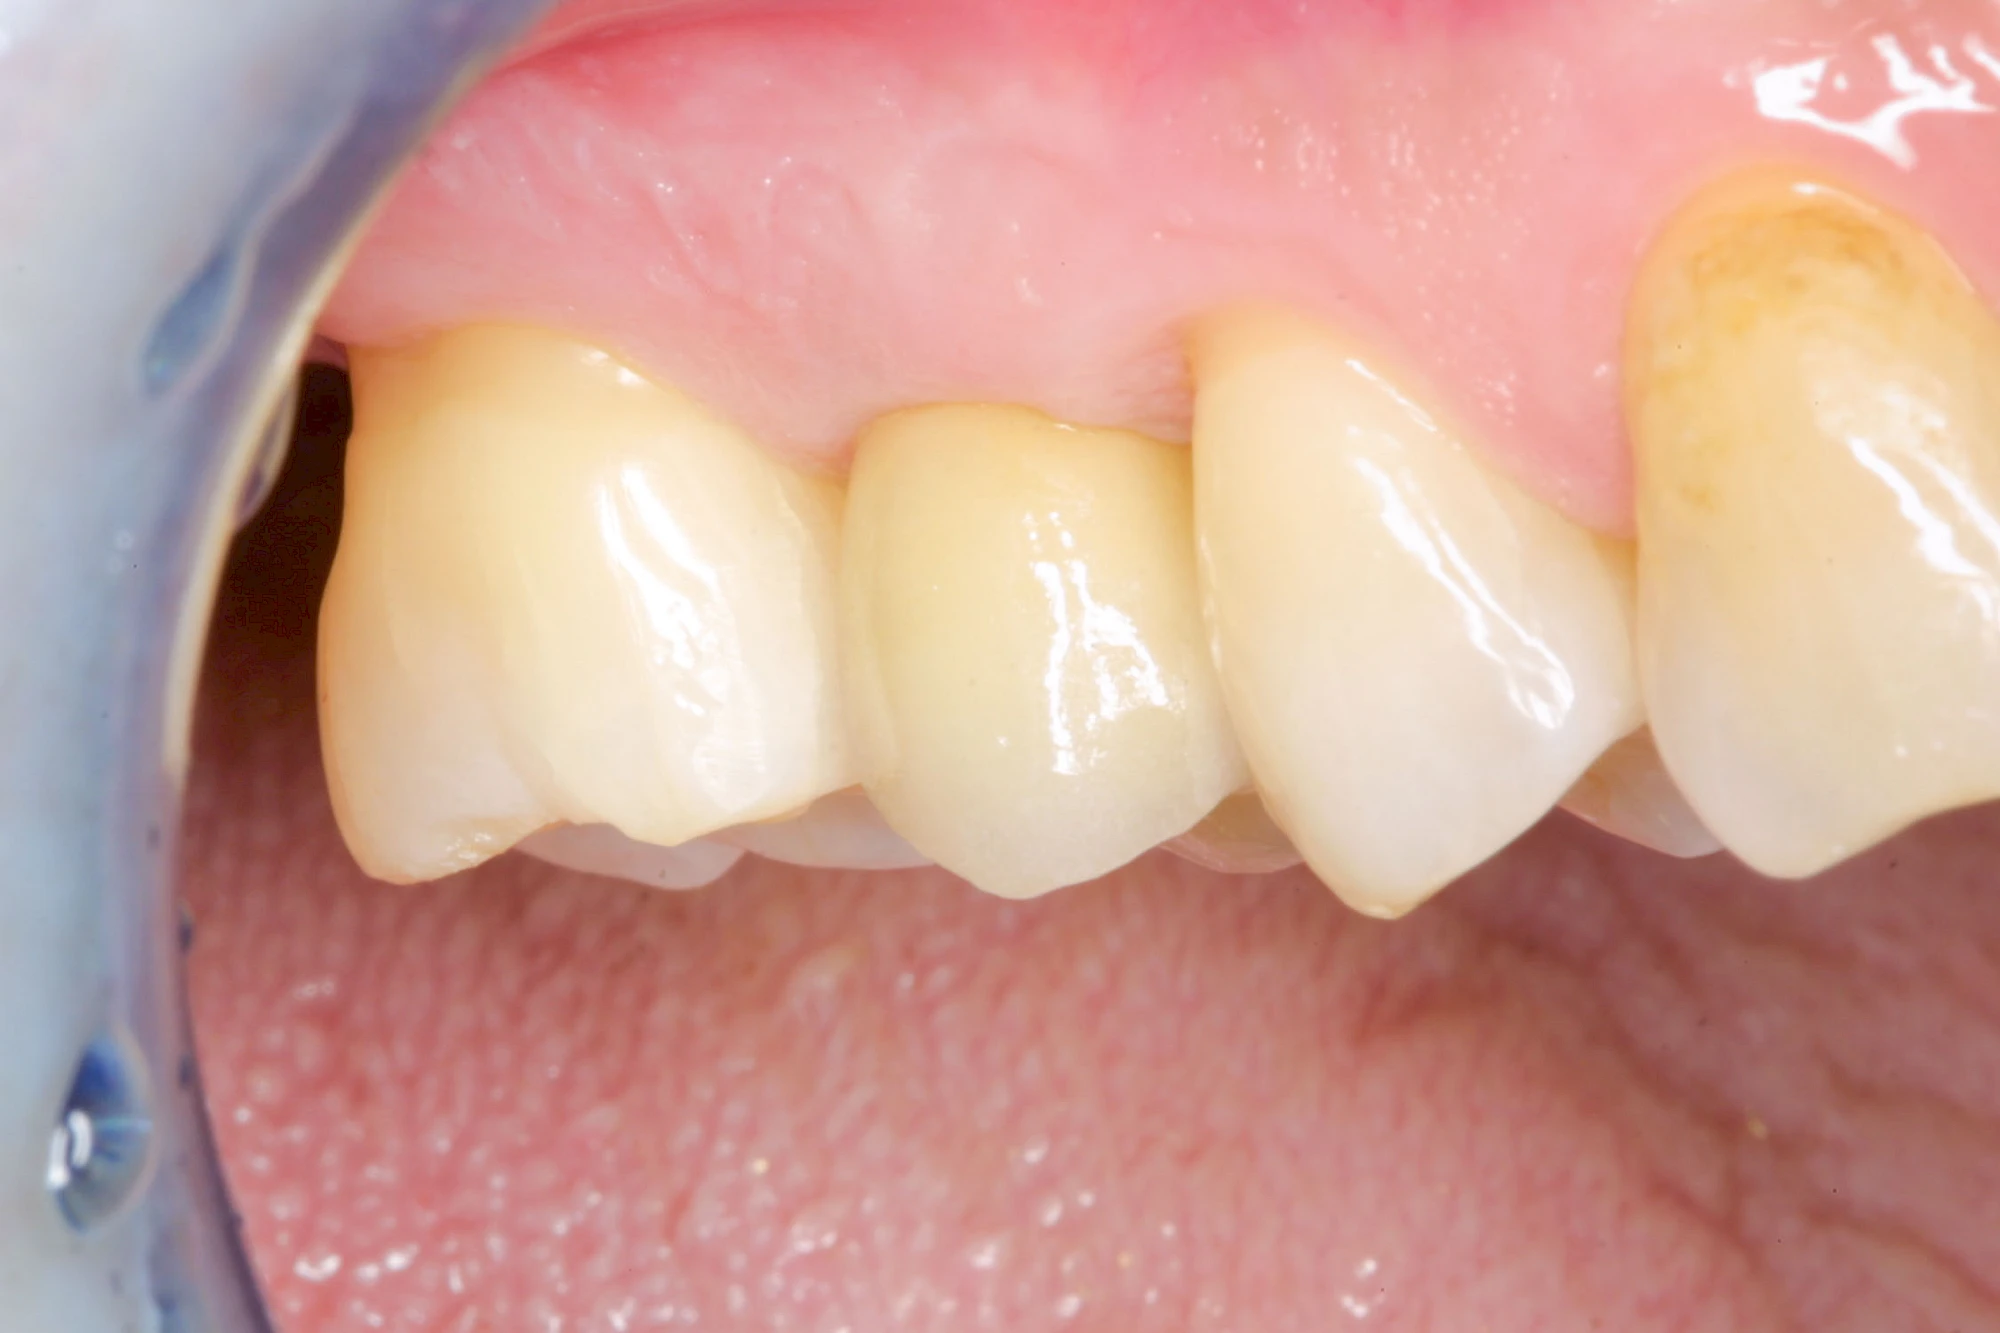

Implantate: Kronen & Brücken

Fehlen einzelne Zähne und die Nachbarzähne sind unbeschadet oder gut zahnärztlich versorgt, werden immer häufiger Implantate gewählt, um die Lücken zu schließen. Auch bei größeren oder verteilten Lücken, wenn keine herausnehmbare Prothese gewünscht ist, werden Implantate für Kronen- bzw. Brückenversorgungen gesetzt. In Einzelfällen entscheiden sich sogar zahnlose Patienten für eine festsitzende Versorgung auf Implantaten.

Varianten zur Verankerung von festsitzendem Zahnersatz auf Implantaten